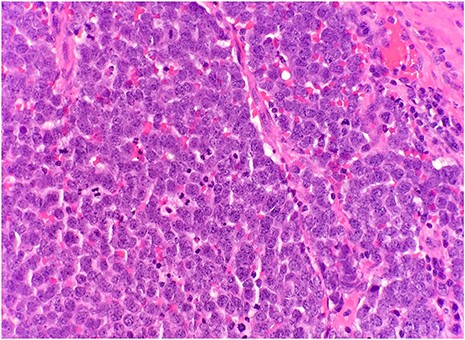

After surgical excision, specimen was received by pathology in formalin and consisted of a fragment of pink-tan dense tissue measuring 6.5 × 5.5 × 4 cm. The cut section revealed a fresh and necrotic surface. Microscopic examination revealed nests of monotonous round tumor cells with infiltration of the subcutis. Tumor cells had a scant eosinophilic cytoplasmic rim and round, vesicular nuclei with abundant mitotic figures (Fig. 1) and neuroendocrine features (CD56 and Synaptophysin positive) (Fig. 2). Immunohistochemical stain CK20 demonstrated paranuclear dot-like staining, consistent with MCC (Fig. 3). Negative staining for CD45 excluded lymphoma. The tumor demonstrated positive margins with vascular invasion.

Immunohistochemical stain reveals that tumor cells are positive for synaptophysin (IHC × 20).